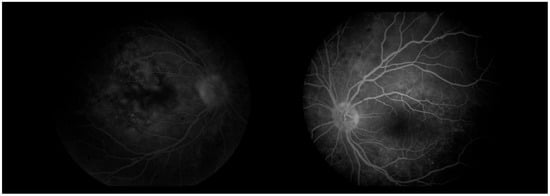

Figure 17. Analysis protocol “HD 21 Line” of the right and left eye.